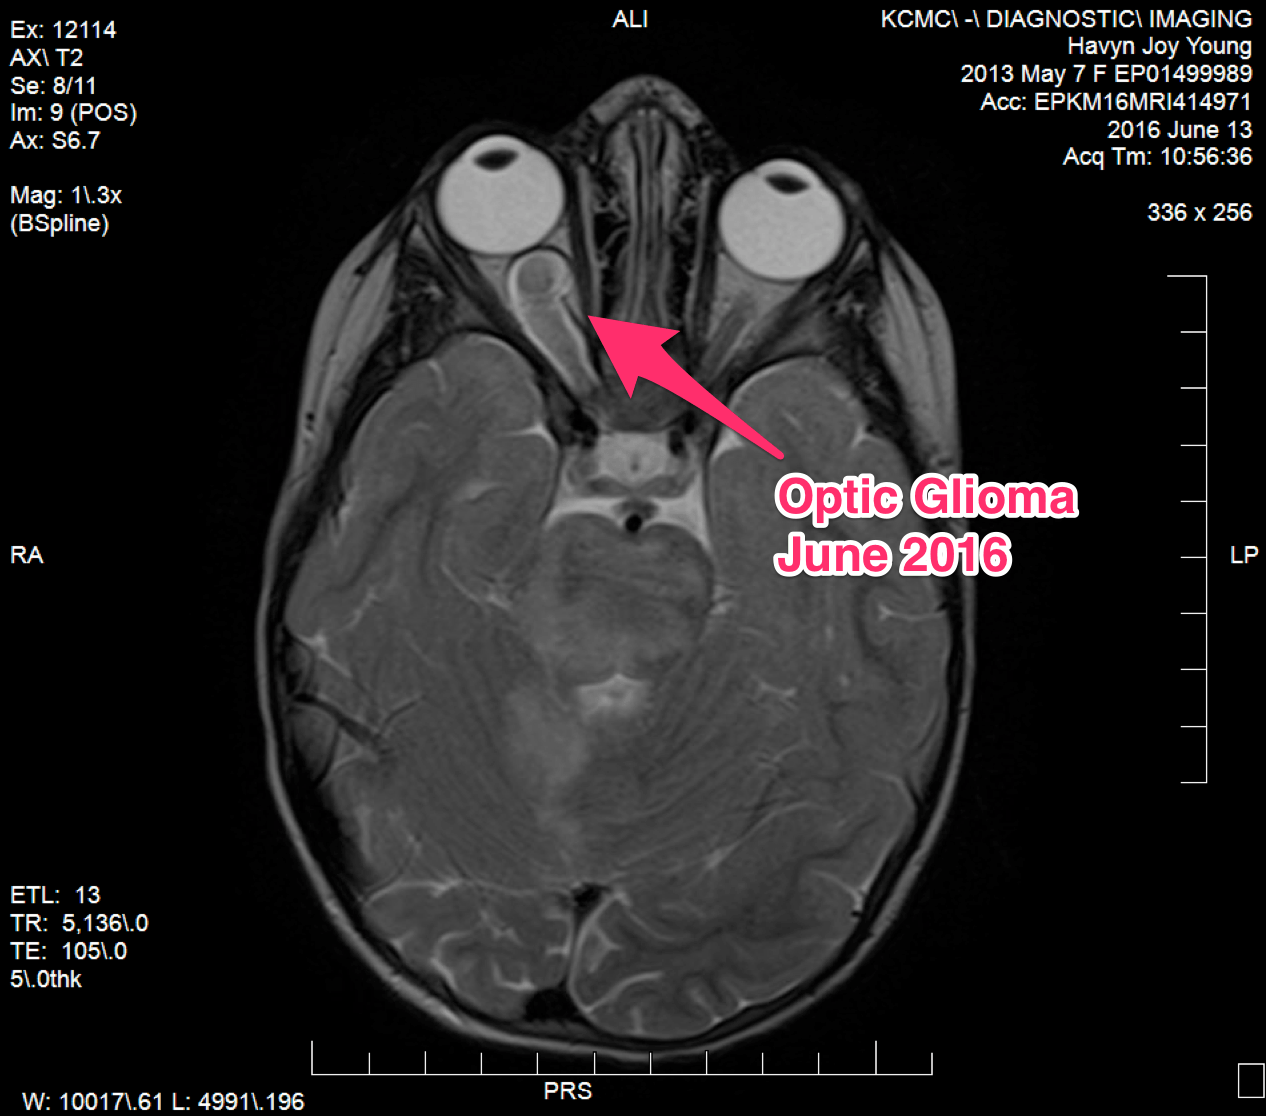

Optic Glioma – June 2016